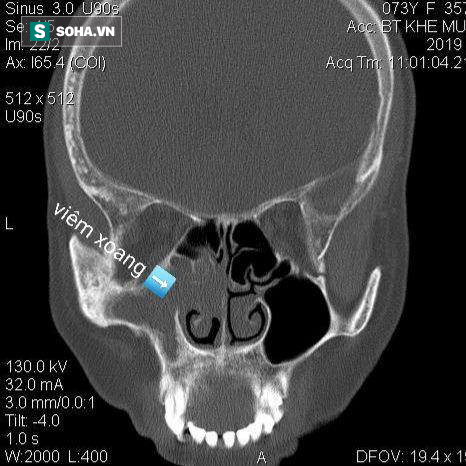

Hình ảnh chụp viêm xoang của bệnh nhân Đ, BSCC.

Bác sĩ Tuấn cho hay, mới đây bác sĩ cũng tiếp nhận điều trị cho trường hợp bệnh nhân Lương Thị Đ (62 tuổi, Dương Nội, Hà Đông, Hà Nội) tới khám trong tình trạng đau đầu vùng hốc mắt, trán, đỉnh bên trái đau âm ỉ liên tục, kèm theo chảy nước mũi đã được khoảng 10 ngày.

Sau khi, được chỉ định làm nội soi mũi xoang thì bác sĩ phát hiện Polyp mũi xoang hàm, tụ dịch trong xoang trán trái.